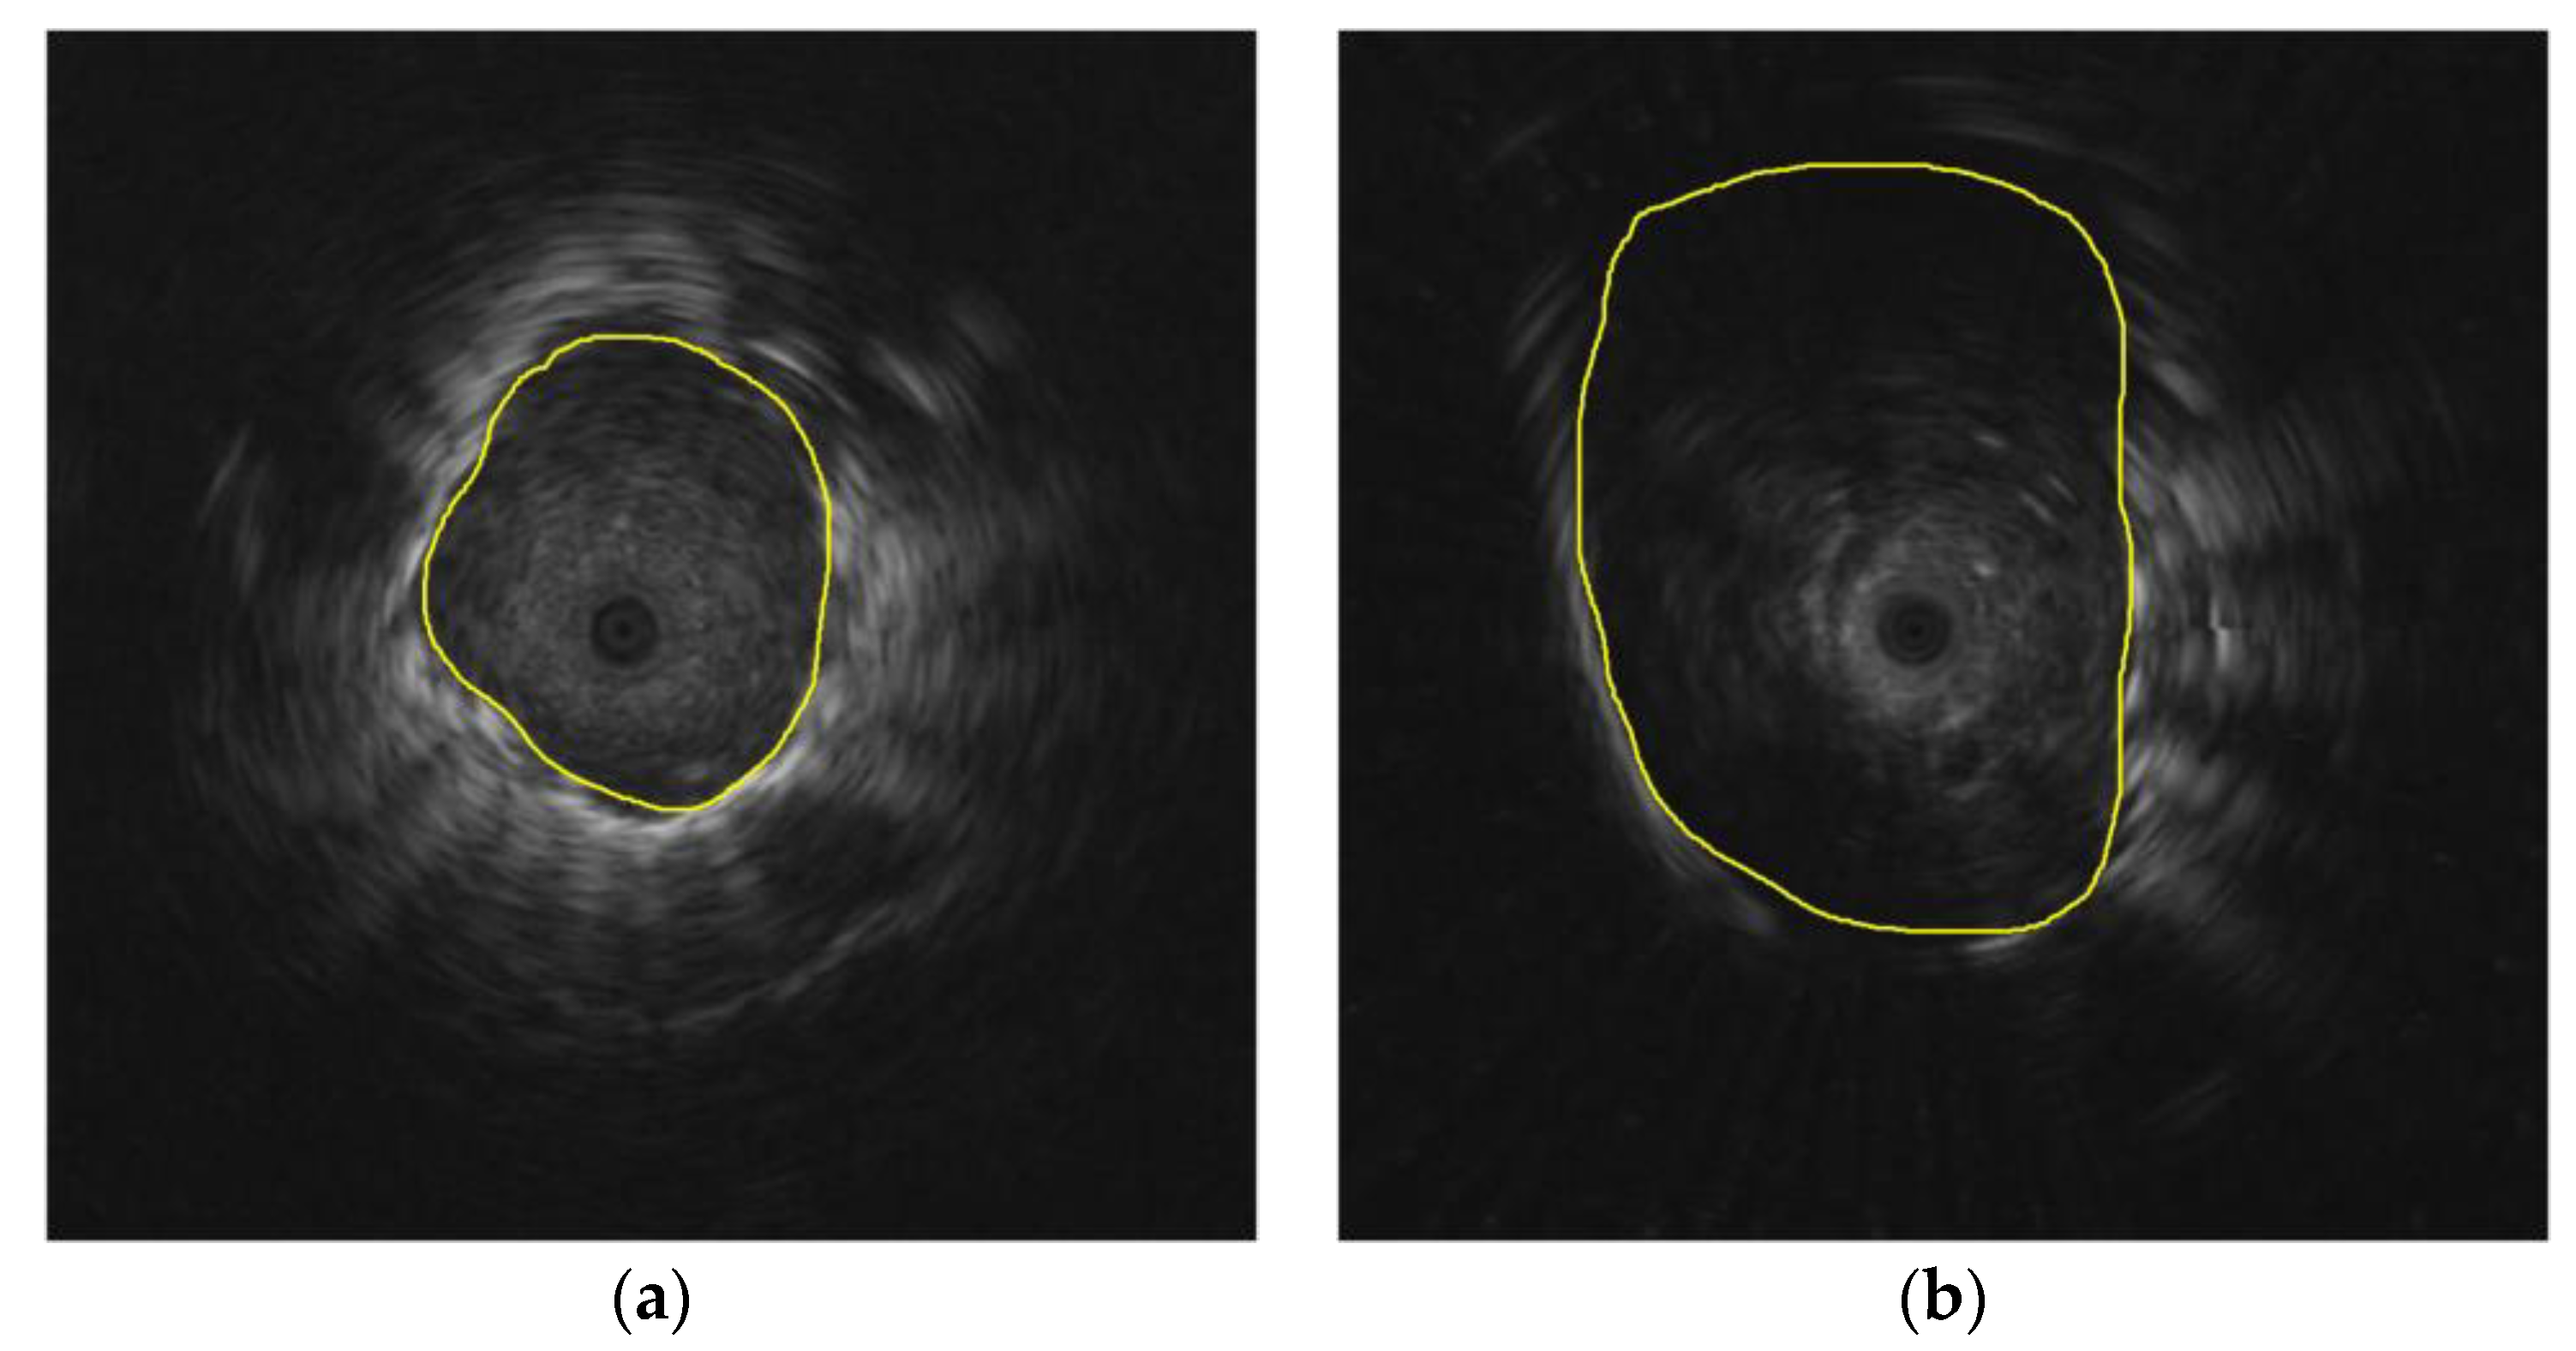

3.1.2. Mask Generation